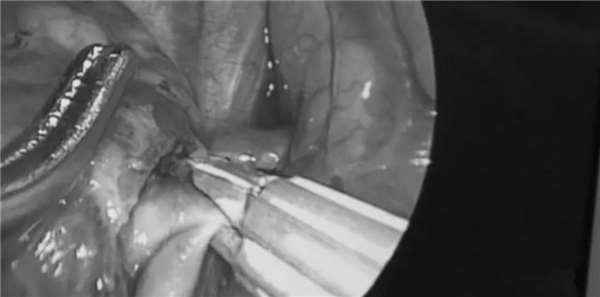

接下來,山高開始尋找靜脈,過了很久,他又在黏合在一起的肺葉深處發現了一條4公分長的靜脈。

終於找到了,那麼按部就班之前的操作就好了吧,結紮,剪斷,然後切除肺葉?

然而,此時的山高卻無比緊張,他發現了一個非常重要的問題,因為,就波琦的身體來說,這條靜脈太細了(通常來說,肺靜脈比肺動脈更粗)。

看起來非常奇怪,山高覺得異樣,決定不貿然動手。

他仔細檢查了周圍組織,居然又發現了另一條靜脈!

一般來說,這個位置,應該只有一條靜脈,而波琦的下肺葉這個位置有兩條靜脈的這種情況非常少見。

山高猜測,可能下肺葉裡第一條靜脈太細的緣故,才又長出了第二條靜脈(真正的肺靜脈),要知道,肺靜脈可是向心臟輸送含氧的動脈血的,是維持人呼吸最關鍵的一條靜脈。

這真是千鈞一發的一刻,山高後來回憶到:「如果我沒有找到真正的肺靜脈止住血,而在切除下肺葉時意外割斷了這條肺靜脈,就會造成大出血,那時,我就不得不打開孩子的胸腔了,孩子的心臟很可能隨時停止跳動。」